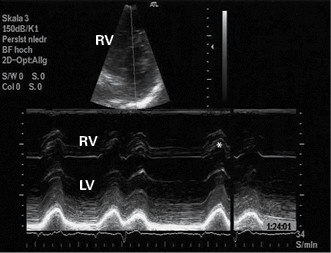

Zur Belastungsplanung führen wir routinemäßig zu Beginn der Rehabilitation eine Echokardiographie zur Erfassung der Rechtsherzbelastung durch. Wir bestimmen hierbei den von uns entwickelten Rechtsherz-Score (R-S). Erfasst werden folgende vier Parameter: Größe des rechten Ventrikels, Kontraktionskraft der freien rechtsventrikulären Wand, Bewegung des Septum interventriculare und Größe des rechten Atriums. Es erfolgt eine quantitative Bewertung mit den Ziffern 1 (normal), 2 (gestört) und 3 (schwergradig gestört). Durch Addition der Einzelwerte und Division durch 4 wird der R-S ermittelt (11; Beispiele Abbildung 1 und 2). Der R-S beträgt 1,0 bei einem Normalbefund und maximal 3,0 bei einer schwersten Rechtsherzbelastung. Nach unseren Untersuchungen geht ein R-S ≥ 2,25 einher mit einer schweren, prognostisch ungünstigen Rechtsherzbelastung, während die Prognose bei einem R-S von < 2,25 günstig ist.